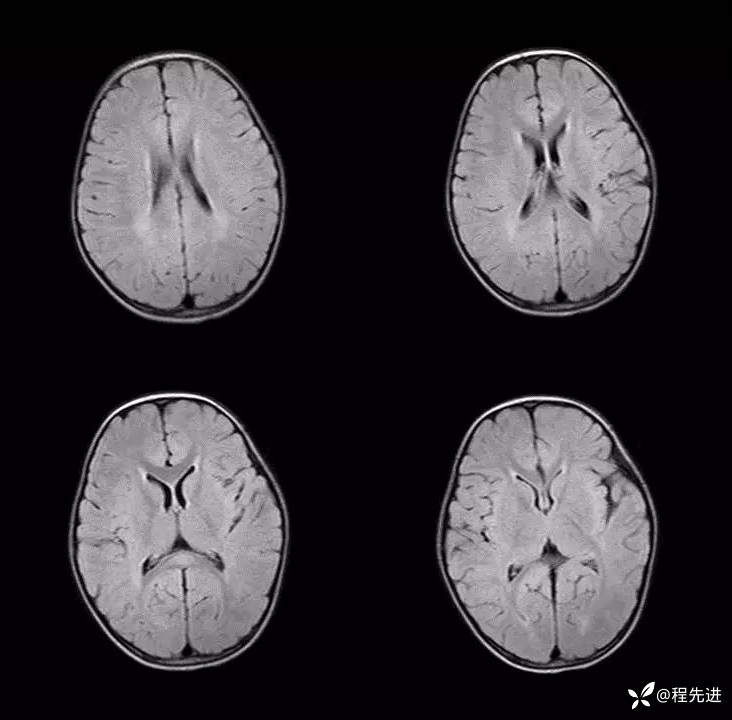

患者性别:女

患者年龄:3岁

主诉:间断呕吐2天,伴腹泻1天,惊厥1次

现病史:2天前进食后呕吐,非喷射状,1天前出现腹泻,每日4-5次。入院2小时前出现抽搐发作

辅助检查:便常规轮状病毒(+)

伴可逆性胼胝体压部病变的轻度脑炎 (7)